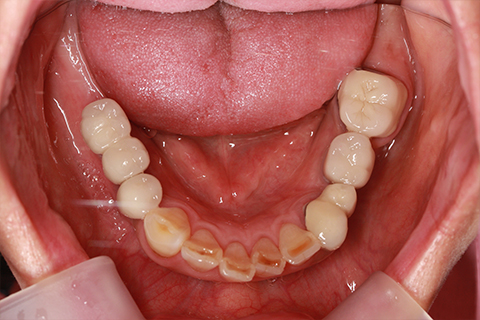

症例5

- 年齢・性別

- 35歳男性

- 治療期間

- 3ヶ月

- 抜歯

- 右上1.3左上6.7の残根抜歯

- 治療費

- 132万円

- 備考

- 右上1.3左上6.7の欠損部

- 治療内容

- 4本のインプラントを一回のオペで埋入。

- 施術の副作用(リスク)

- オペによる知覚障害。インプラントによる歯肉炎。インプラント脱落。